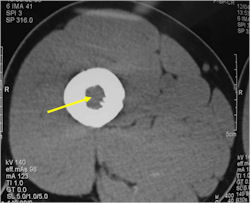

Radiographic Presentation

- Permeative or moth eaten bone destruction

- Ill defined and malignant appearing

- Bony changes are often subtle

- Soft Tissue Mass in 90% of of cases

- Reactive Bone Sclerosis is rare but occurs in 10% of cases

- No cartilage or bone production by tumor